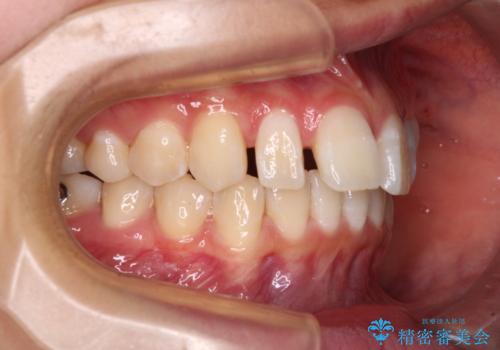

奥歯の咬み合わせを見ると、上顎が下顎に対して相対的に前方にありました。

咬み合わせも深くなっていたため、上顎臼歯を後方に移動させつつ、下顎の小臼歯を直立させ、奥歯の咬み合わせを改善する必要があります。

インビザライン単体で対応することも検討できますが、達成する可能性が低いため、カリエールディスタライザーという補助装置を併用して、より確実性を上げることとしました。

奥歯の咬み合わせと深い咬み合わせを改善した後、隙間などをインビザラインで整えることとしました。